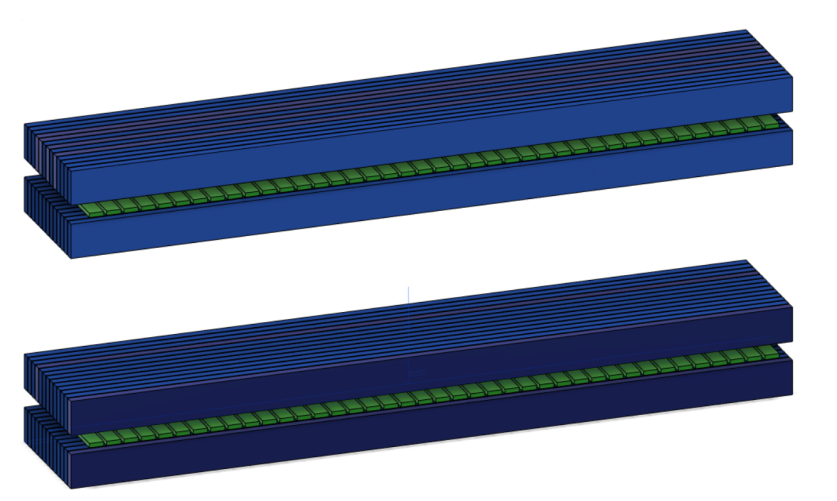

The J-PEM is a prototype intended to evaluate PET technology in the diagnosis of malign neoplasm in the breast and of ganglion loco-regional invasion. It is based on plastic scintillators and utilizes the same technology as the Jagiellonian Positron Emmision Tomograph, J-PET [31]. It is optimized for the detection of photons from electron-positron annihilation [32, 33]. Such photons, having an energy of 511 keV, interact with electrons in plastic scintillators predominantly via the Compton effect. J-PEM uses a dedicated instrument for breast cancer detection that is equipped with two parallel photon detectors in a configuration similar to mammography compressors. The detector system consists of two modules of plastic scintillators, with each module built from two layers of plastic scintillator and the wavelength shifters [34, 35] placed orthogonally between them, as shown in Fig. 6. Each scintillator bar is attached at both ends with Silicon Photomultipliers for the signal readout [32]. The combined use of plastic scintillators, which have superior timing properties, with the WLS strips can provide an affordable and precise scanner with significant improvement in spatial resolution and efficiency for the detection of breast cancer. Plastic scintillators are characterized by short light decay time which is in the order of 1.5 ns [32]. This enables one to achieve high time resolution. In the J-PET, solution for the position of the interaction point of photons is based on the measurement of the time of the signals arrival to the ends of the long scintillator strips. So far a resolution of about 10 mm was achieved [35]. In order to achieve high resolution, we propose to register scintillation light escaping the scintillator bar through a side wall using an array of WLS. It has been already proven that one can reach to position resolution of 5 mm for the coordinate along the scintillator bar.